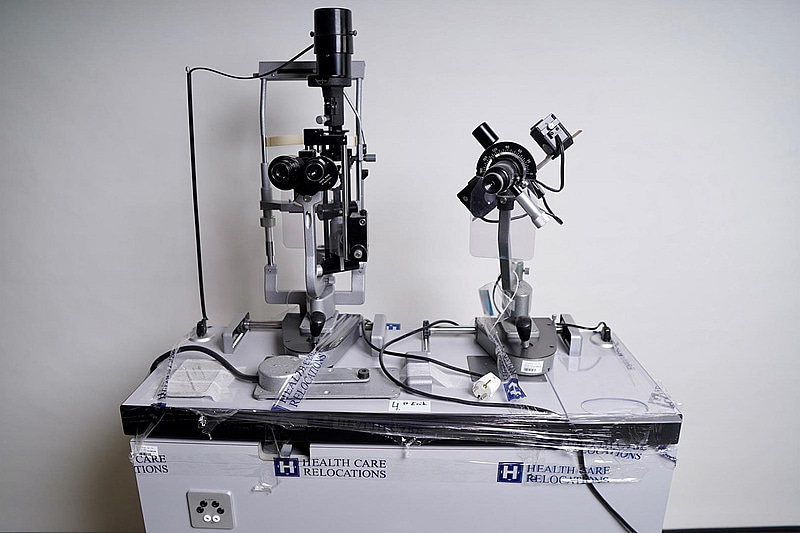

Optiker utrustning, undersökningsbord. Spaltlampa Haag-Streit 900.

Not allowedSpaltlampa Haag Streit 900

Mikroskåp

Dioptrien Haag Streit

Oftamologi/Ophtalmology

B90025223

M90025223

R90028569

The Haag –Streit BM 900 has been the standard in modern slit lamp microscopy for almost 50 years – and still is! Over 100,000 professionals all over the world who own a BM 900 agree that it was the best investment they ever made for their practice. The BM 900 is the “classic” slit lamp for the eyecare professional concerned with both the anterior and posterior segments.

A convergent, stereoscopic microscope offering short observer to patient distances and “workhorse” 10 and 16 X magnifications (with standard 10 X eyepieces – optional eyepieces with other magnifications are available – see “Accessories”). PD and optical correction are both finely adjustable to give easy viewing with none of the eye fatigue so often associated with use of the slit lamp.

The Cross Slide Mechanism incorporated into all Haag –Streit slit lamps, has both vertical and horizontal movements controlled by our patented joystick. Perfection in design, materials and construction allow these movements to be made smoothly and effortlessly without any wrist or finger strain – and to continue so for the very long lifetime of this classic slit lamp.

The illumination system has the brightest (600,000 Lux) illumination available in a slit lamp providing a tilting, rotating slit up to 8 mm in length and width.

Tilting is extremely important to good posterior segment observation. All filter and slit controls are conveniently situated for ease of use and, as with the cross slide mechanism, have silky smooth, effortless movement. The slit mechanism, on of those “differences inside”, is a masterpiece of engineering in itself, affording faultless precision in both shape and movement. Imaging A “through the eyepiece” digital adaptor for the BM 900 is available.